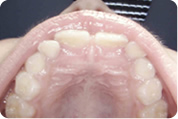

Intraoralna kamera

Prikaz zuba intraoralnom kamerom pod povećanjem i do 60 puta omogućuje nam uvid u stanje svakog pojedinog zuba i precizno planiranje radova. Jednako tako važna je i mogućnost jasnog prikaza zubnih lukova u cjelini i prikaza plana terapije našim pacijentima.